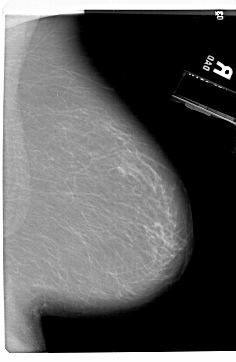

A_1450_1.LEFT_CC

LEFT_CC LINES 6871 PIXELS_PER_LINE 4306 BITS_PER_PIXEL 12 RESOLUTION 43.5 OVERLAY

FILE: A_1450_1.LEFT_CC.OVERLAY

TOTAL_ABNORMALITIES 1

ABNORMALITY 1

LESION_TYPE MASS SHAPE LOBULATED MARGINS CIRCUMSCRIBED

ASSESSMENT 3

SUBTLETY 3

PATHOLOGY BENIGN

TOTAL_OUTLINES 1

BOUNDARY